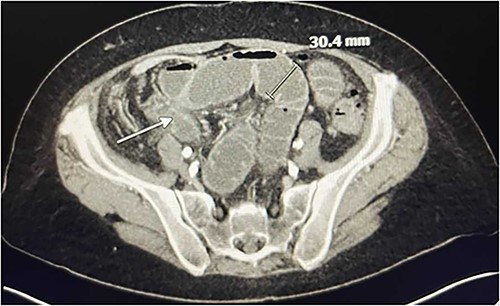

CT Angiography showing SBO with transition point in the right lower quadrant. A loop of thickened ileum measures 30.4 mm. The white arrow points to a stricture.

In the emergency department on presentation to our hospital, her vital signs were unremarkable and laboratory results were notable for a white blood cell count of 13 600 with left shift to 86% neutrophils. She underwent a computed tomography (CT) angiogram, which revealed an occluded SMA, severe celiac artery stenosis (nearly 90%), and a patent IMA (Fig. 1). A high-grade SBO was noted, possibly secondary to stricture, with transition point in the right lower quadrant (Fig. 2).